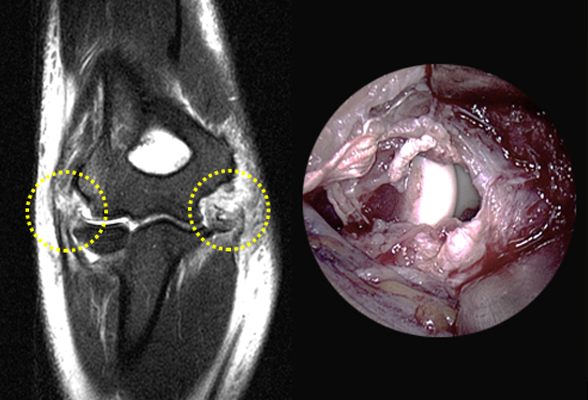

테니스 엘보 / 골프 엘보

팔꿈치에서 시작되는 근육에 염증이 발생되거나 파열되는 질환인

테니스 엘보(외측 상과염) 또는 골프 엘보 (내측 상과염)은

운동 선수들에게 증상이 주로 나타났으나 최근에는 일반인에게도 많이 나타나는 질환입니다.

비수술 치료 : 교정치료(보조기), 물리치료, 주사치료, 도수치료